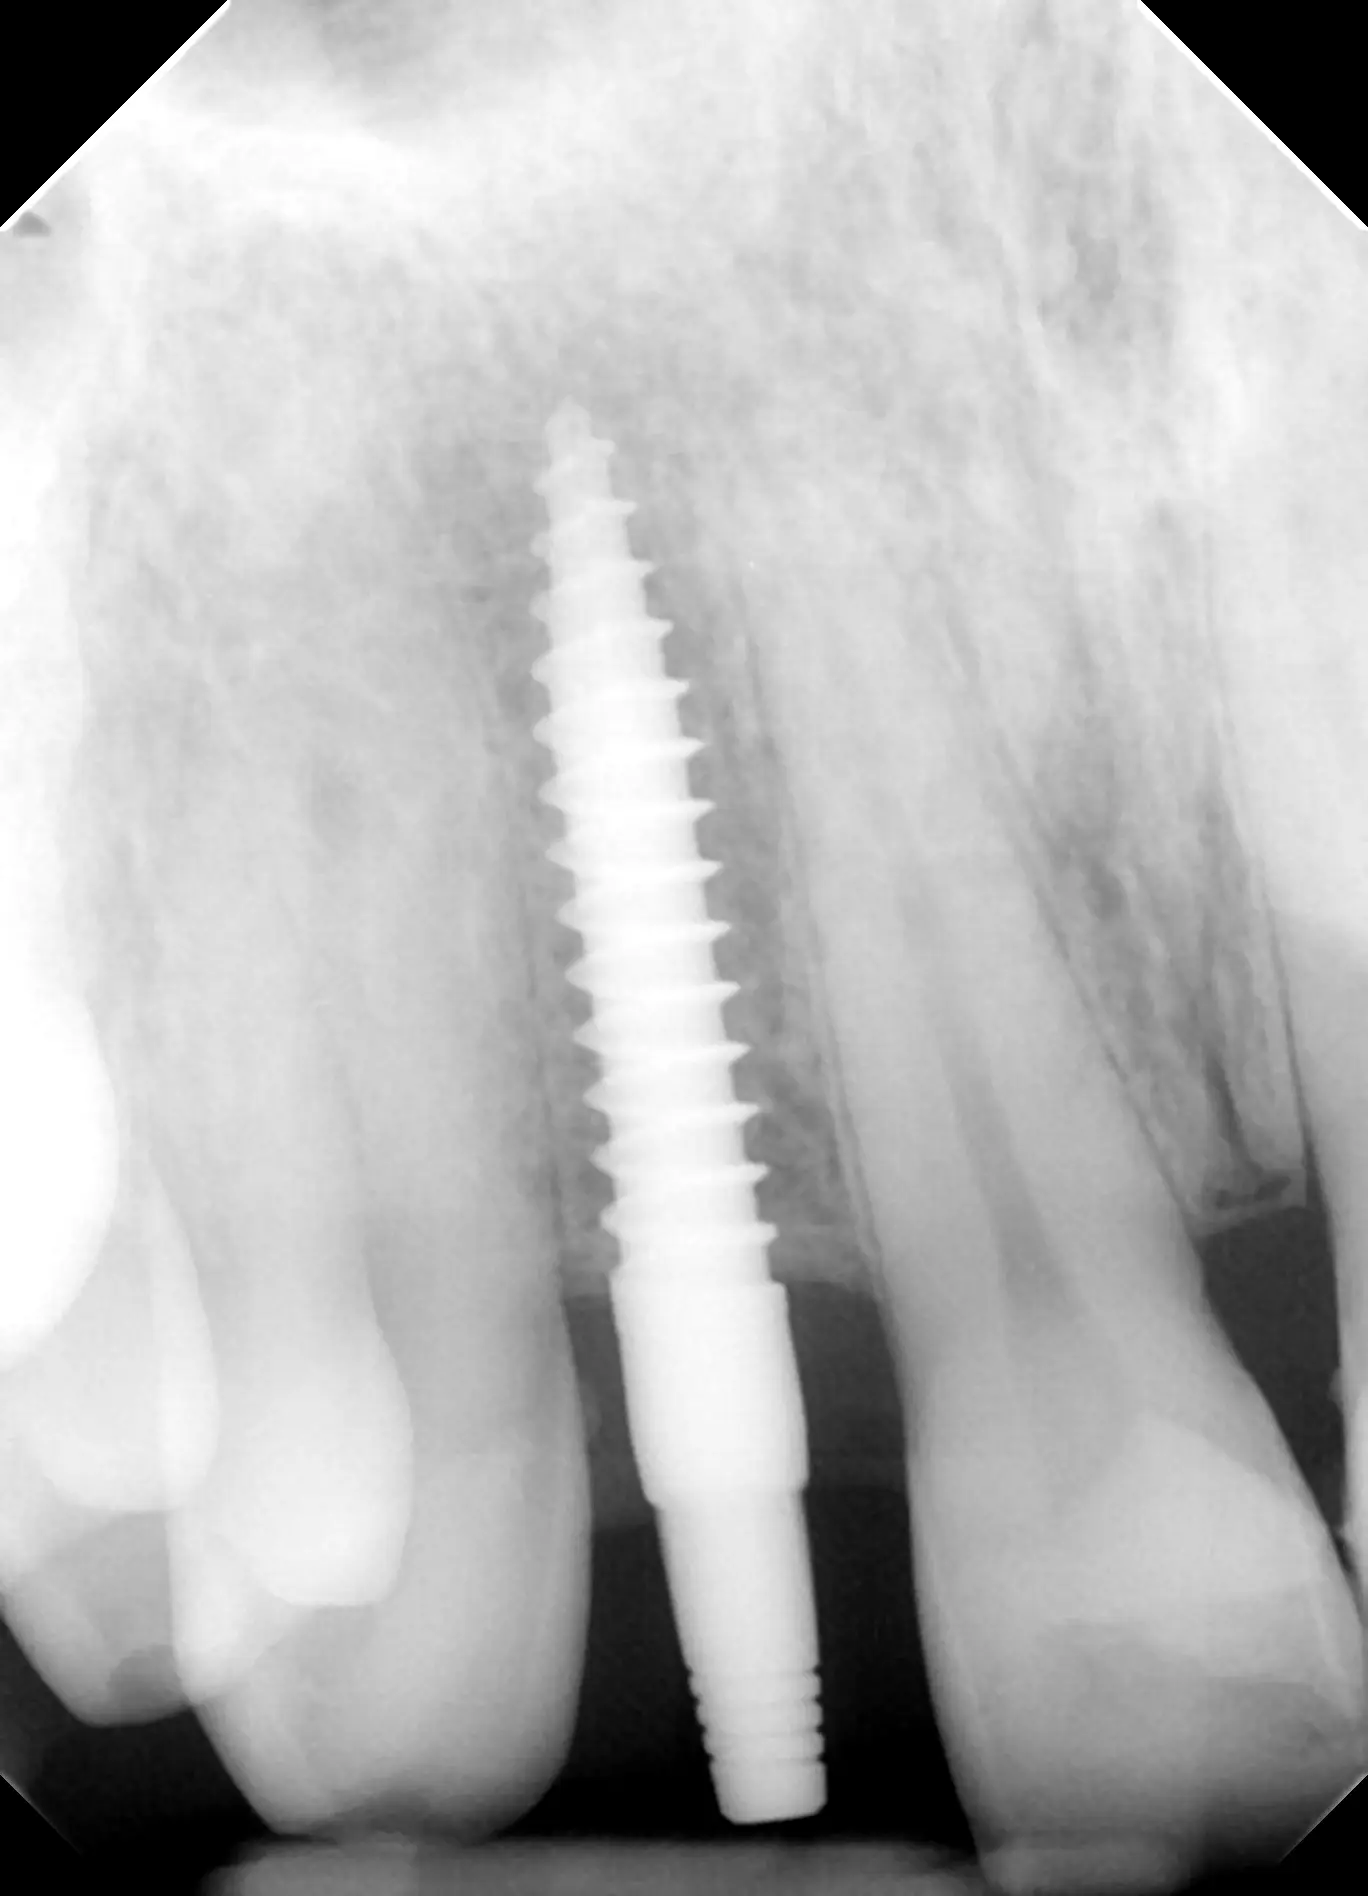

Narrow implant Placement to replace a front tooth

The patient had a “Maryland” bridge which would break or fall out every few years. Prior dentists told him he could not get a dental implant.

A 3D scan was taken to measure the bone. Although a bit limited in space for an implant, there was enough space to place an implant if done very precisely.

A narrow implant was Placed by Dr. Peter Mann.

Patient left the office with a temporary crown after his implant placement.

A few weeks later a porcelain crown was cemented to create a beautiful esthetic smile. The outcome in this case was tremendous.